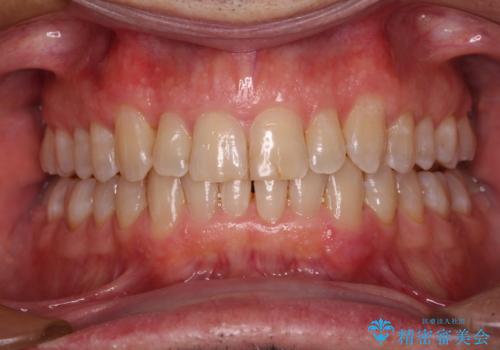

【モニター】前歯のデコボコを治したい インビザライン矯正治療

- 前歯のデコボコを気にして来院された患者様です。

インビザラインでもワイヤー装置でも対応可能でしたが、仕事の都合で来院回数を減らしたいとのことでインビザラインによる矯正治療を選択されました。

著しく咬合力が強いため、奥歯がしっかりと噛めずに治療が長引くことが懸念されました。

1セット目のインビザラインを使用した際には左右ともに大臼歯が咬み合っていなかったのですが、2セット目できっちりと仕上げることができました。